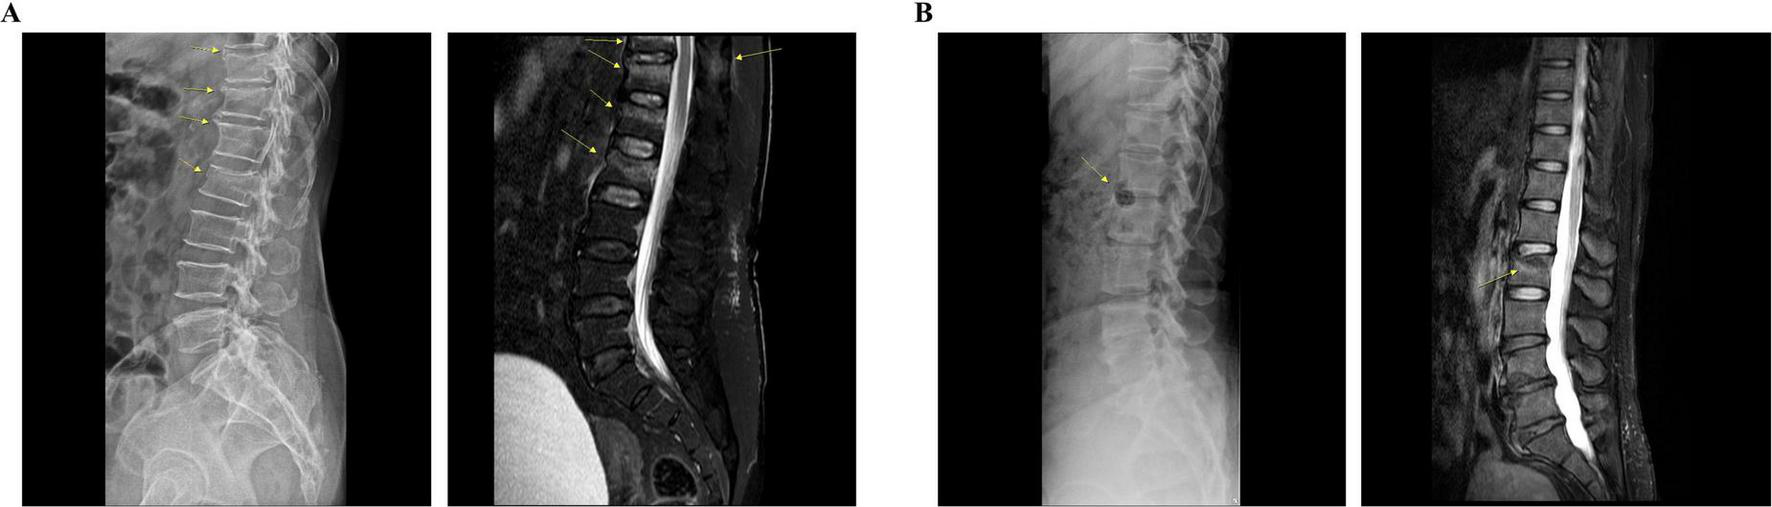

The diagnosis of VCF was confirmed via radiography and magnetic resonance imaging (MRI) during the admission period (Figures 1, 2). Patient 1 was a 68-year-old woman with a history of hyperlipidemia, hypertensive heart disease, and osteoporosis. Radiography and MRI confirmed recent compression fractures at the T11–L2 vertebral body (Figure 2A). She reported severe thoracolumbar pain radiating to the chest, which was exacerbated by coughing and frequent sleep disruption. Meanwhile, Patient 2 was a 49-year-old woman without any medical history; she presented with acute L2 vertebral body compression fracture (Figure 2B). She complained of severe back pain, nausea, and diarrhea, which disrupted her sleep. Both patients had unremarkable psychosocial and genetic histories. Other than a one-time administration of analgesics following the onset of symptoms, discontinued upon hospital admission, there were no relevant prior interventions.

FIGURE 2

Radiological findings of each patient. (A) Patient 1: lateral radiograph reveals subtle bone deformities, including radiolucent lines, extending from T11 to L2. Sagittal T2-weighted fat-saturated MRI shows low signal intensity lines with bone marrow edema in the T12, L1, and L2 vertebral bodies, indicative of recent fractures. Additionally, a recent fracture can be observed at the T11 vertebral body, accompanied by bone marrow edema in the spinous process. (B) Patient 2: lateral radiograph reveals bone lesions, including a hypo-dense lesion in the anterior column of the L2 vertebra. Sagittal T2-weighted fat-saturated MRI demonstrates a compression fracture with bone marrow edema in the L2 vertebral body. MRI, magnetic resonance imaging.

As summarized in Figure 1, both patients were initially on bed rest, followed by gait training with a supporting device as soon as possible. Analgesic medication was administered alongside conservative therapies and prospectively planned to maintain sleep quality, which is a crucial factor in bone mineral density and fracture recovery (23). With continuous treatment, both patients were able to stand and walk using a walker in the second week (Figure 1). However, the improvement in NRS and ODI was greater in Patient 2, indicating better prognosis (Figure 3). As expected, Patient 1 had a higher number of fractured vertebral bodies, including spinous process fractures, and more severe vertebral collapse, leading to a longer bed rest period and greater analgesic use than Patient 2 (Figures 1, 2). A multicenter cohort study reported that patients with acute vertebral fractures who received only bracing without any other treatment required up to 12 weeks to ensure full pain relief and QoL improvement (24). In this context, the return to daily activities after approximately 4 weeks of treatment in both our patients suggests a relatively earlier recovery of pain and function than the expected course of VCF healing.